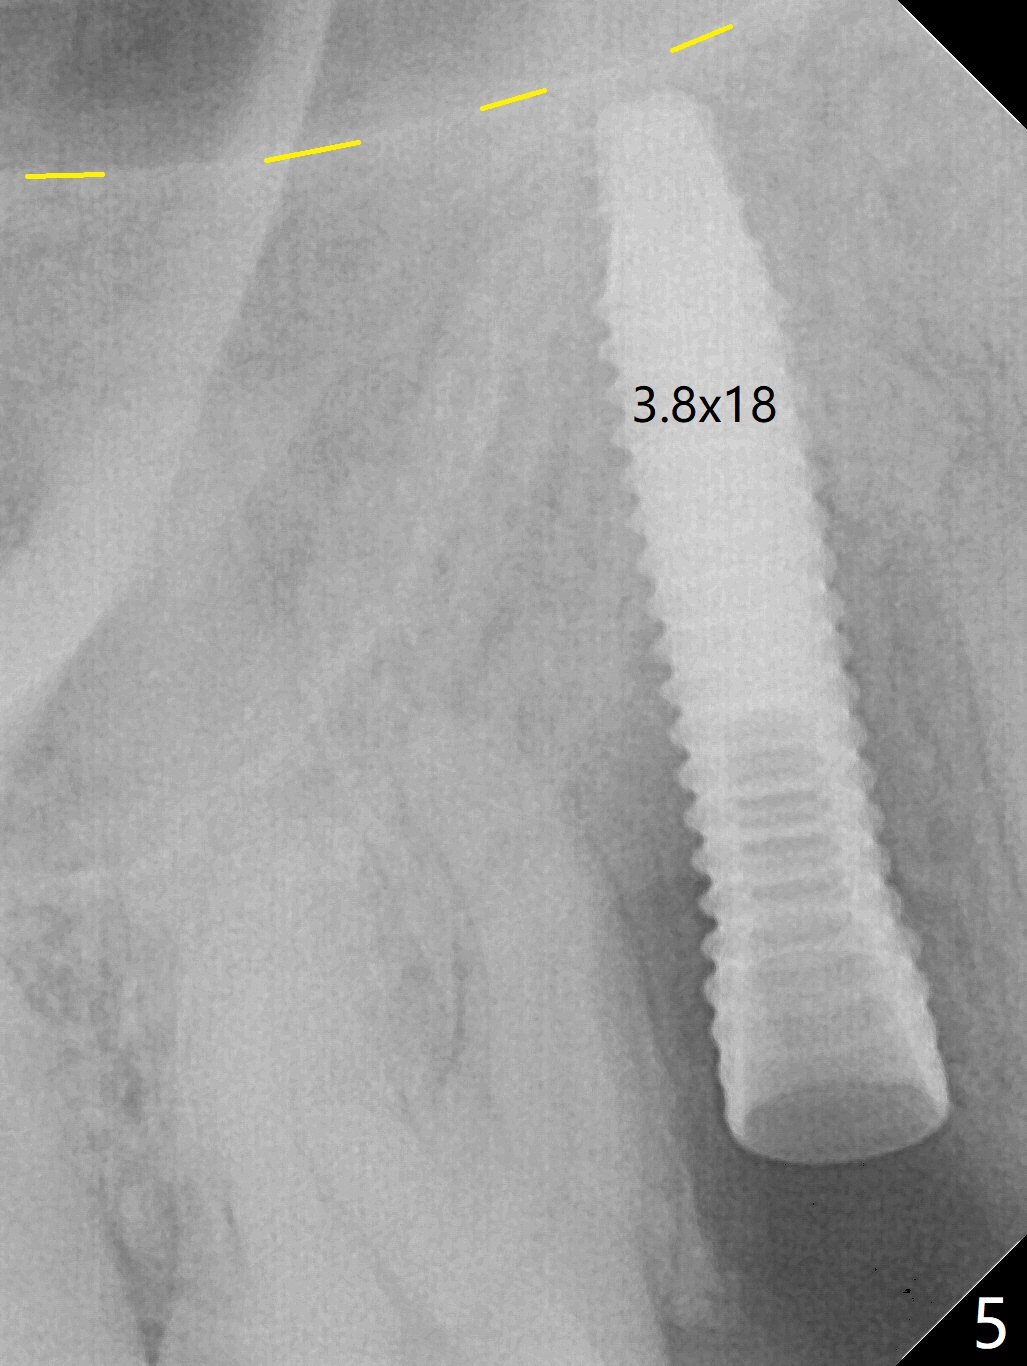

When the tooth #4 with vertical root fracture (Fig.1) is extracted, the buccal plate is found to be lost. The lowest point of the defect is shown as black dashed line in Fig.2 (yellow dashed line: sinus floor). After use of 2.5 mm reamer for 21 mm (buccal gingival level) and 3.0 mm reamer for ~17 mm, a 3.8x15 mm dummy implant is placed with 30 Ncm and 1.85 mm apical space (Fig.3 pink outline). A 3.8x18 mm (definitive) implant is placed with <40 Ncm with the implant plateau apical to the lingual crest (Fig.4,5). The buccal plate defect is repaired by Vanilla Graft (Fig.6 *) before and after insertion of a 4.5x4(3) mm abutment. The buccal plate defect seems to being repaired 4 months postop (Fig.7). Occlusal wear suggests bruxism, which is also associated with the root fracture. Night guard is recommended. The defect repair is close to completion 8 months post cementation (Fig.8). The crown/abutment is found to be loose 1 year 4 months post cementation and retightened without checking whether there is clinical 2nd DO caries of #3 (Fig.9, "sensitive to water pik"). A few days later, DO composite is being removed. It is difficult to determine whether the 2nd DO caries or gap has been removed with the neighboring crown in place. When the crown/abutment is removed and gingival retractions are inserted, there is no decay. The gap is removed. With Toflemire in place, the crown/abutment is reseated and hand tightened; after packable composite, the crown/abutment is removed, there is no more DO gap.

In fact there is a small buccal fistula, which is communicated with the underlying implant threads. Although preop CT shows that the buccal crest is lower than the palatal (3.8x13 mm, Fig.10 P) one, intraop finding of missing buccal plate should dictate a shorter implant (Fig.11) or onlay graft to avoid periimplantitis. Regeneration of the bone plate is limited. Later the fistula disappears with formation of a concavity (Fig.13). There is no symptom. Is bone graft necessary with a remote incision? 3-D images of CT taken 1 year 5 months post cementation show possible mesiobuccal and distopalatal bony defects (Fig.13-16). It is possible that bone graft was placed enough palatal (Fig.16). DO composite at #3 is redo satisfactorily (Fig.17 *).